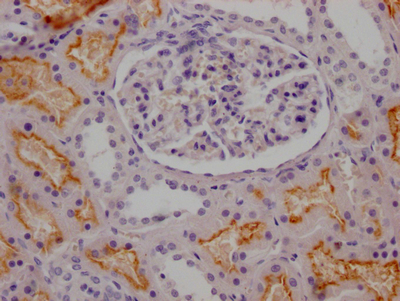

IHC image of CSB-RA268157A0HU diluted at 1:100 and staining in paraffin-embedded human kidney tissue performed on a Leica BondTM system. After dewaxing and hydration, antigen retrieval was mediated by high pressure in a citrate buffer (pH 6.0). Section was blocked with 10% normal goat serum 30min at RT. Then primary antibody (1% BSA) was incubated at 4℃ overnight. The primary is detected by a Goat anti-rabbit IgG polymer labeled by HRP and visualized using 0.05% DAB.